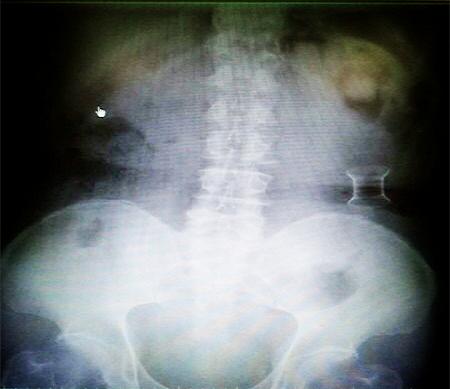

受試患者在結腸端端吻合術中,使用我司新研制產品達到了理想的預期效果。患者術后7天、14X光片顯影,可降解腸道支架均能按研制設計的預期時間節點保持應有強度,術后21X光片顯示可降解腸道支架已完全破碎,并排出體外。在整個試驗過程中,病患無任何不良反映,耐受良好。